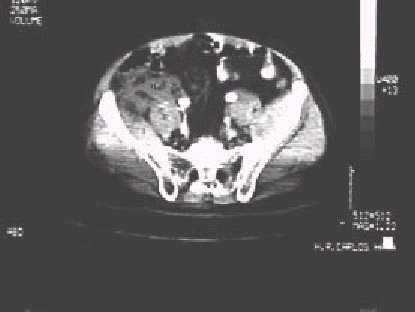

—Hematoma retroperitoneal en una Tomografía Computerizada de un paciente con fractura de pelvis. P = músculo psoas, Y = músculo Ilíaco y H = Hematoma.